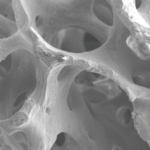

Lately, various surface treatment methods have been studied to facilitate rapid and strong osseointegration. According to the surface roughness and topography, the surface chemistry plays an important role for osseointegration. Titanium (Ti) and Ti alloys are bioinert surfaces and are not able to directly bond with bone. One method for increasing surface reactivity is to coat the Ti surface with nanostructured calcium. Many in vitro and in vivo studies have already reported the effectiveness of nanostructured calcium coating.

For example, in vitro studies have reported that surface modification using calcium ions increased the growth of osteoblastic cells and promoted the precipitation of apatite on Ti surfaces in simulated body fluid. Plus, the effects of cell adhesion to calcium-incorporated Ti surfaces were reduced in human alveolar bone cells and MG-63 cells, and increased in human osteoblasts. Several in vivo studies have reported that incorporating calcium into Ti implants by hydrothermal treatment stimulated osseointegration by increasing the BIC % when compared with untreated Ti implants in rabbit models.

1. Nano bone matrix layer of Ca2+ -incorporated S-L-A surface

Ca2+ is incorporated into the fixture structure to create a CaTiO3 nano-structure. This then forms a unique & uniform nano-structure with Ca2+ions, which activate osteoblasts in living organisms.